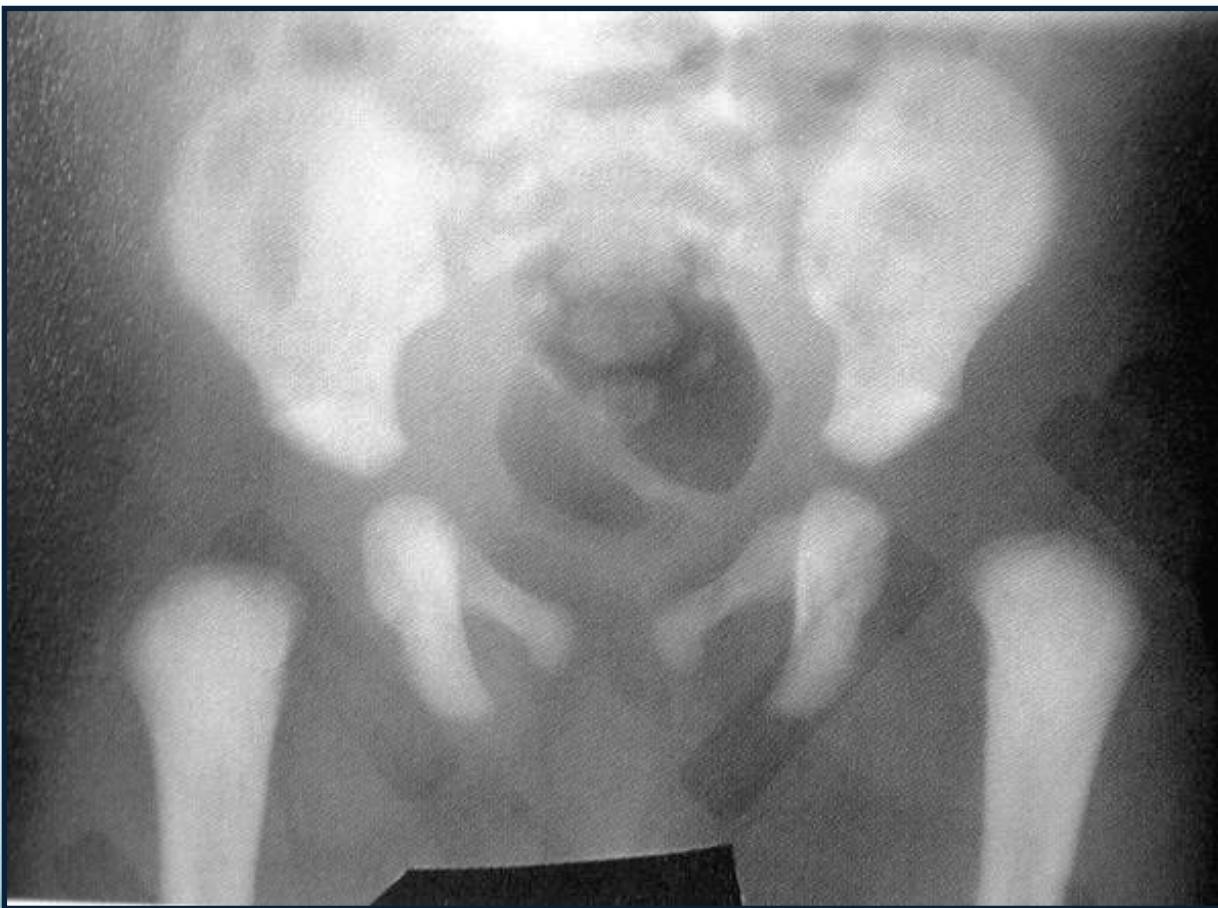

After 6 months:

- Clearly shows dislocation

- Size of femoral head ossific center

- Horizontal line through the tri-radiate cartilage

Position Assessment:

- Dislocated: Above the horizontal line

- Normal: Below the horizontal line